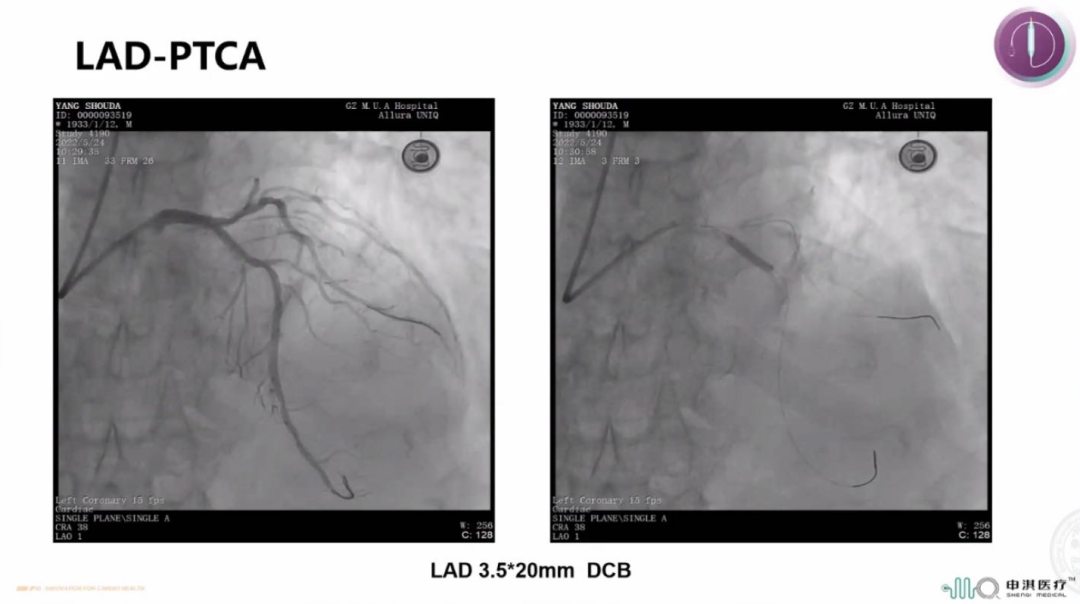

该患者为90岁高龄男性,既往有PCI史,且合并糖尿病、高血压、慢性肾功能不全。冠脉造影示LCX支架内次全闭塞,合并重度钙化;LAD近中段弥漫狭窄。手术过程中首先对LAD行IVUS检查示MSA 3.45mm²,可见表浅的钙化斑块。ISR是DCB的IA类适应症,于是术者在进行充分预处理后首先使用申淇3.0*30mm DCB扩张LCX-ISR病变80s。LAD病变弥漫,且患者为高出血风险,于是同样选择申淇3.5*20mm DCB治疗LAD病变,手术即刻效果满意。